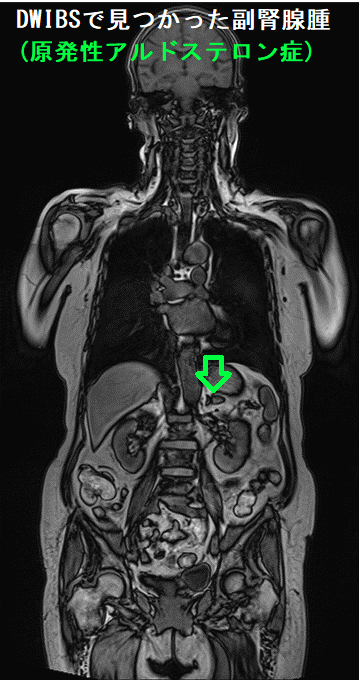

全身拡散強調MRI検査(DWIBS:ドゥイブス )で副腎偶発腫瘍(インシデンタローマ)を見つける場合があります。

写真は、甲状腺濾胞癌手術後の遠隔転移検索で行った全身拡散強調MRI検査(DWIBS:ドゥイブス )の際、偶然見つかった副腎腺腫(原発性アルドステロン症)。